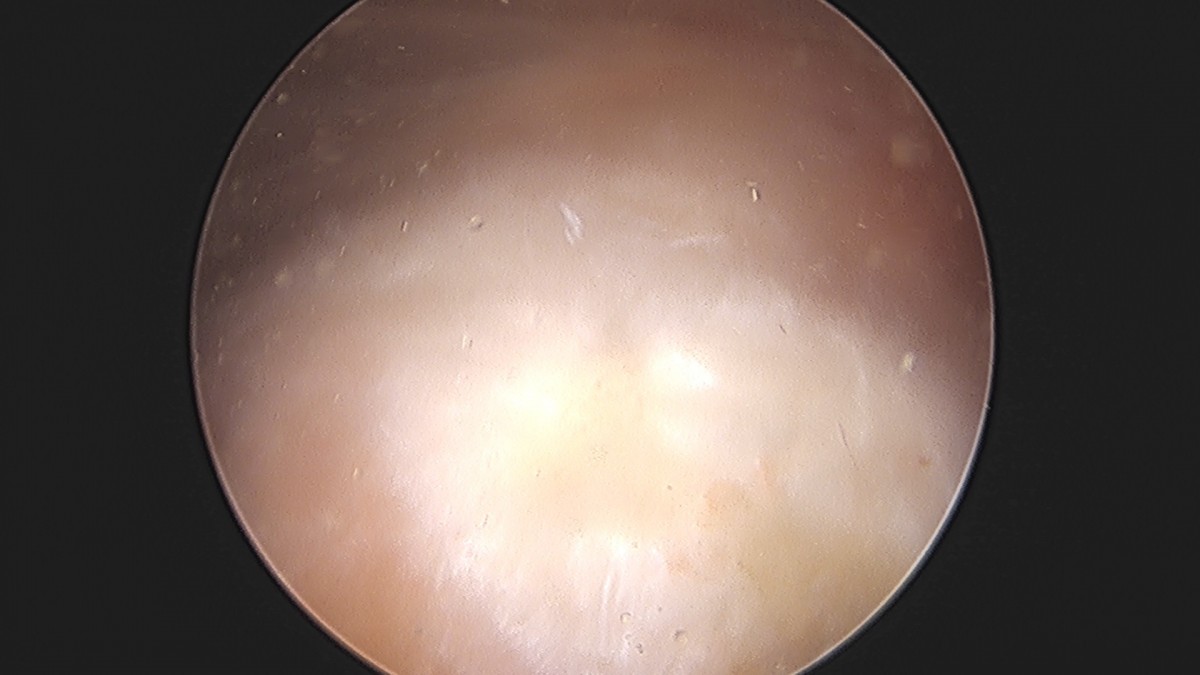

이재상원장님 어깨 견봉하 감압술 및 석회 제거술 이형O 환자

dae765e4d9ac96aee867c9d6292d8784_1758004811_5774.jpg

dae765e4d9ac96aee867c9d6292d8784_1758004812_1603.jpg

dae765e4d9ac96aee867c9d6292d8784_1758004812_7437.jpg

dae765e4d9ac96aee867c9d6292d8784_1758004813_474.jpg

dae765e4d9ac96aee867c9d6292d8784_1758004814_0674.jpg

dae765e4d9ac96aee867c9d6292d8784_1758004814_6645.jpg

dae765e4d9ac96aee867c9d6292d8784_1758004815_2588.jpg

dae765e4d9ac96aee867c9d6292d8784_1758004815_8533.jpg

dae765e4d9ac96aee867c9d6292d8784_1758004816_4696.jpg

dae765e4d9ac96aee867c9d6292d8784_1758004817_0509.jpg